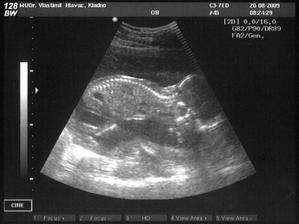

* 20.8.2009: konečně zase ultrazvuk, srdce, mozek, žaludek, močový měchýř - všechno zdá se funguje a mrňousek kopal o sto šest! A hlavně výsledky na protilátky jsou povzbudivé, od minule nevzrostly! A další důležité zjištění: čekáme CHLAPEČKA!!!